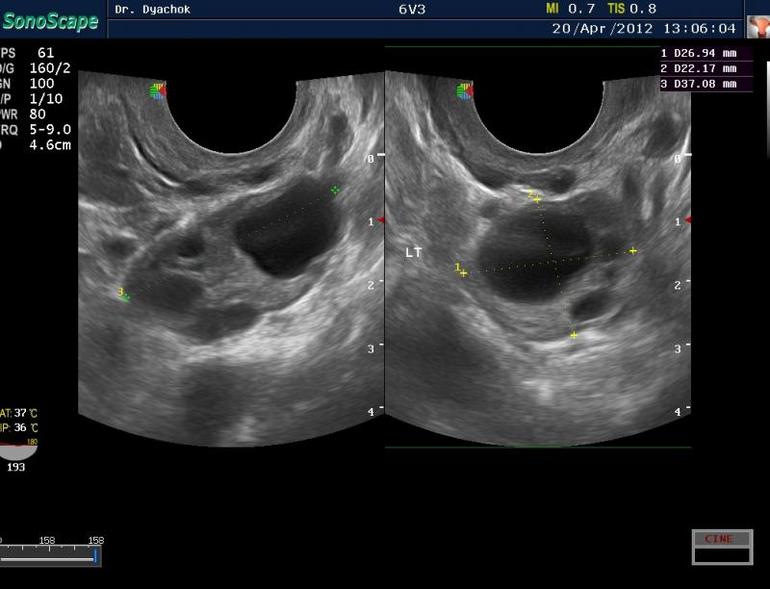

При МФЯ вот:

С доминантным так:

Вот у меня всегда была верхняя картинка. А сейчас он мне делает УЗИ и я вижу нижнюю, третью картинку. У моего врача кстати в кабинете прикольно. Ложишься на кушетку, а у тебя в ногах сверху прилеплен монитор, на котором все отображается. Лежишь, короче, и не напрягаясь смотришь че там как у тебя внутри._)))))